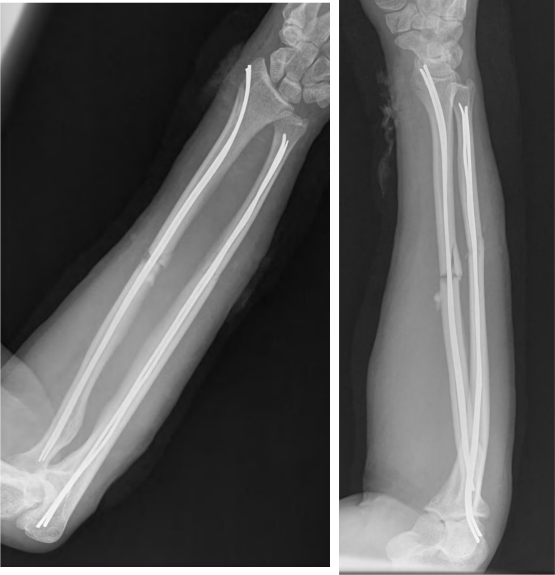

Radius Ulna-Plating Nail

“Plating Nail” likely refers to orthopedic implants used in fracture fixation or orthopedic surgeries. These devices are designed to stabilize fractured bones, promote healing, and restore normal anatomical alignment. The term can encompass various types of implants, including plates and nails, commonly used in orthopedic procedures.